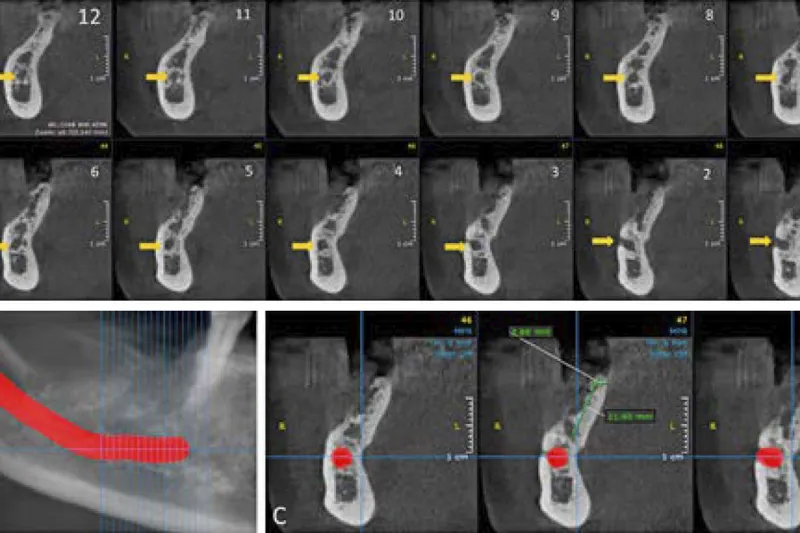

Atrofi af den posteriore mandibel byder på udfordringer, når en eller flere manglende tænder ønskes erstattet med en implantatbaseret protetisk restaurering. Behandlingsstrategi afhænger af flere faktorer, herunder dimensionerne af processus alveolaris samt beliggenheden af relevante anatomiske strukturer i mundbunden og mandiblen. Lokalisation af canalis mandibulae er således yderst vigtigt i forbindelse med implantatindsættelse i den atrofiske posteriore mandibel, da intraoperativ beskadigelse af n. alveolaris inferior vil medføre neurosensoriske forstyrrelser bl.a. svarende til hagen og underlæben. Omhyggelig behandlingsplanlægning inklusive radiologisk identifikation af canalis mandibulae er derfor afgørende for valg af relevant behandlingsmodalitet ved protetisk rehabilitering af den atrofiske posteriore mandibel og at gennemføre behandlingen med et forudsigeligt og sikkert behandlingsresultat med god langtidsprognose og mindst mulig risiko for komplikationer. I nærværende oversigtsartikel gennemgås forskellige metoder til vurdering af det tandløse område posteriort i mandiblen før implantatbehandling, herunder røntgenundersøgelse med særlig fokus på anvendelse af CBCT til lokalisering af canalis mandibulae.

Atrophy of the posterior mandible presents challenges, when one or more teeth are to be replaced with an implant-based prosthetic restoration. The treatment strategy is influenced by several factors, including the dimensions of the alveolar ridge as well as the location of relevant anatomical structures in the floor of the mouth and the mandible. Localization of the mandibular canal is therefore of utmost importance in relation to implant placement in the atrophic posterior mandible since injury to the inferior alveolar nerve may cause neurosensory disturbances of the chin and lower lip. Thus, careful treatment planning, including radiological identification of the mandibular canal is essential for the selection of relevant treatment modality for prosthetic rehabilitation of the atrophic posterior mandible as well as conducting the treatment with a predictable and safe treatment outcome with a good long-term prognosis and the lowest risk of complications. In the present review, various methods for assessment of the edentulous area in the posterior mandible prior to implant treatment, including radiographic examination with special focus on the use of CBCT for localization of the mandibular canal are presented.